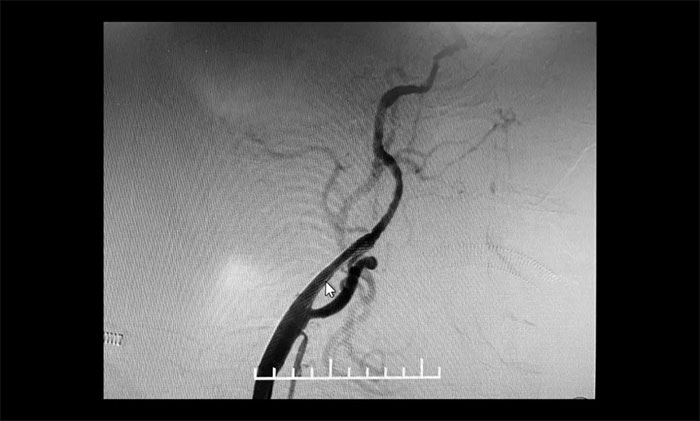

术后康复观察一月余,于耀宇主任团队再次为曹老伯行右侧颈动脉支架置入及左侧椎动脉支架置入手术。术中造影显示,右侧颈内动脉起始段重度狭窄,狭窄长度8mm左右。左侧椎动脉 V4 段重度狭窄,长度6mm左右。运用娴熟扎实的技术,在充分做好脑保护的前提下经过多次球囊扩张后,顺利释放支架于狭窄处。造影提示支架打开良好,血管狭窄基本恢复正常,支架贴壁佳,支架内血流通畅,远端血流良好。

▲ 术后,右侧颈内动脉及左侧椎动脉狭窄明显改善